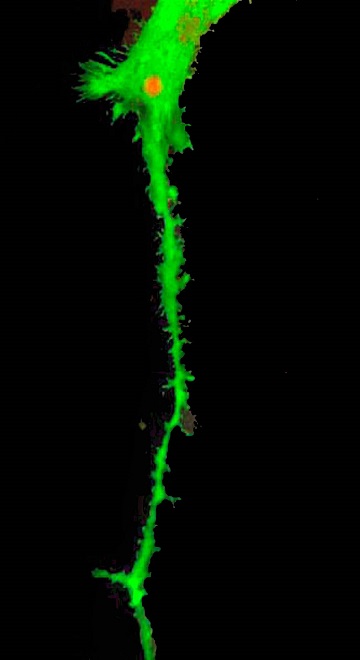

In the peripheral nervous system, we have focused on the therapeutic potential of Schwann cells to jump start recovery. Schwann cells are a vital part of the peripheral nervous system, they nourish and repair nerves, and provide the myelin lining to speed signal conduction. One of our senior scientists has published research showing that we can take bone marrow cells and transform them into these useful Schwann cells—a discovery that may lead to injection of the cells into injured nerves to facilitate regeneration in peripheral nerves that have been damaged due to acute spinal cord injury, limb compartment syndrome, or diseases like diabetes and multiple sclerosis.